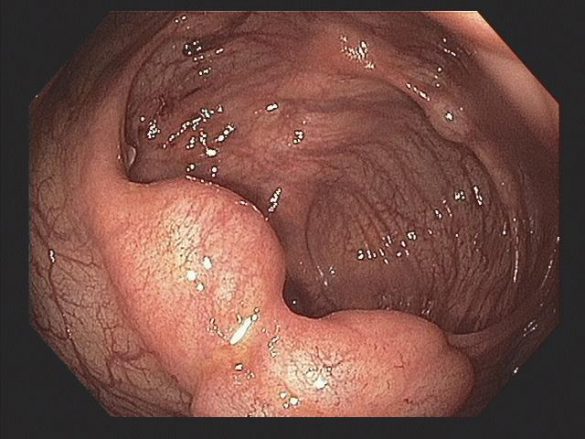

A PI pode afetar o intestino delgado, cólon ou ambos. Os cistos podem estar confinados à mucosa, submucosa ou subserosa, ou envolver todas as três camadas. Cistos subserosos são mais comumente vistos na pneumatose do intestino delgado, enquanto os cistos submucosos são mais comumente vistos na pneumatose cólica (como no caso em questão).

A PI pode ser descoberta incidentalmente na colonoscopia e deve-se prosseguir a investigação com ultrassonografia endoscópica. Cistos variam em tamanho de alguns milímetros a vários centímetros. Os cistos da submucosa costumam ter uma aparência pálida ou azulada e, quando biopsiados, podem desinflar rapidamente com um chiado audível.